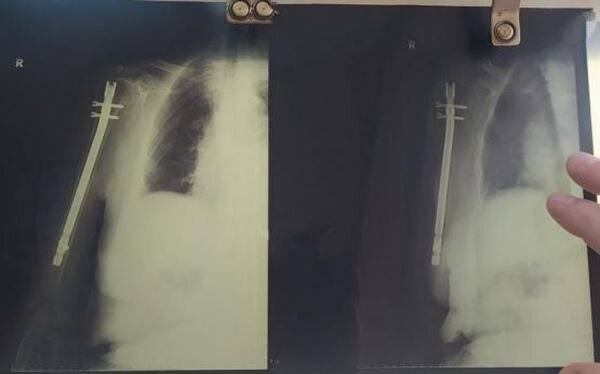

Это хирургический метод восстановления длинных трубчатых костей: через небольшие кожные разрезы в поврежденное место вводится специальный штифт, фиксирующий костные отломки. Зона перелома в процессе операции не открывается, что позволяет сохранить кровоснабжение и обеспечивает возможность быстрого сращивания перелома.

- Очень важно, что после проведения такой операции пациенту не требуется гипс и какие-либо сковывающие повязки. Что немаловажно для возрастных людей. Человек выписывается на пятый день после поступления. И далее наблюдается амбулаторно по месту жительства, - рассказал врач травматолог-ортопед отделения травматологии № 1 ГБСМП Ростова-на-Дону Олег Литвиненко.